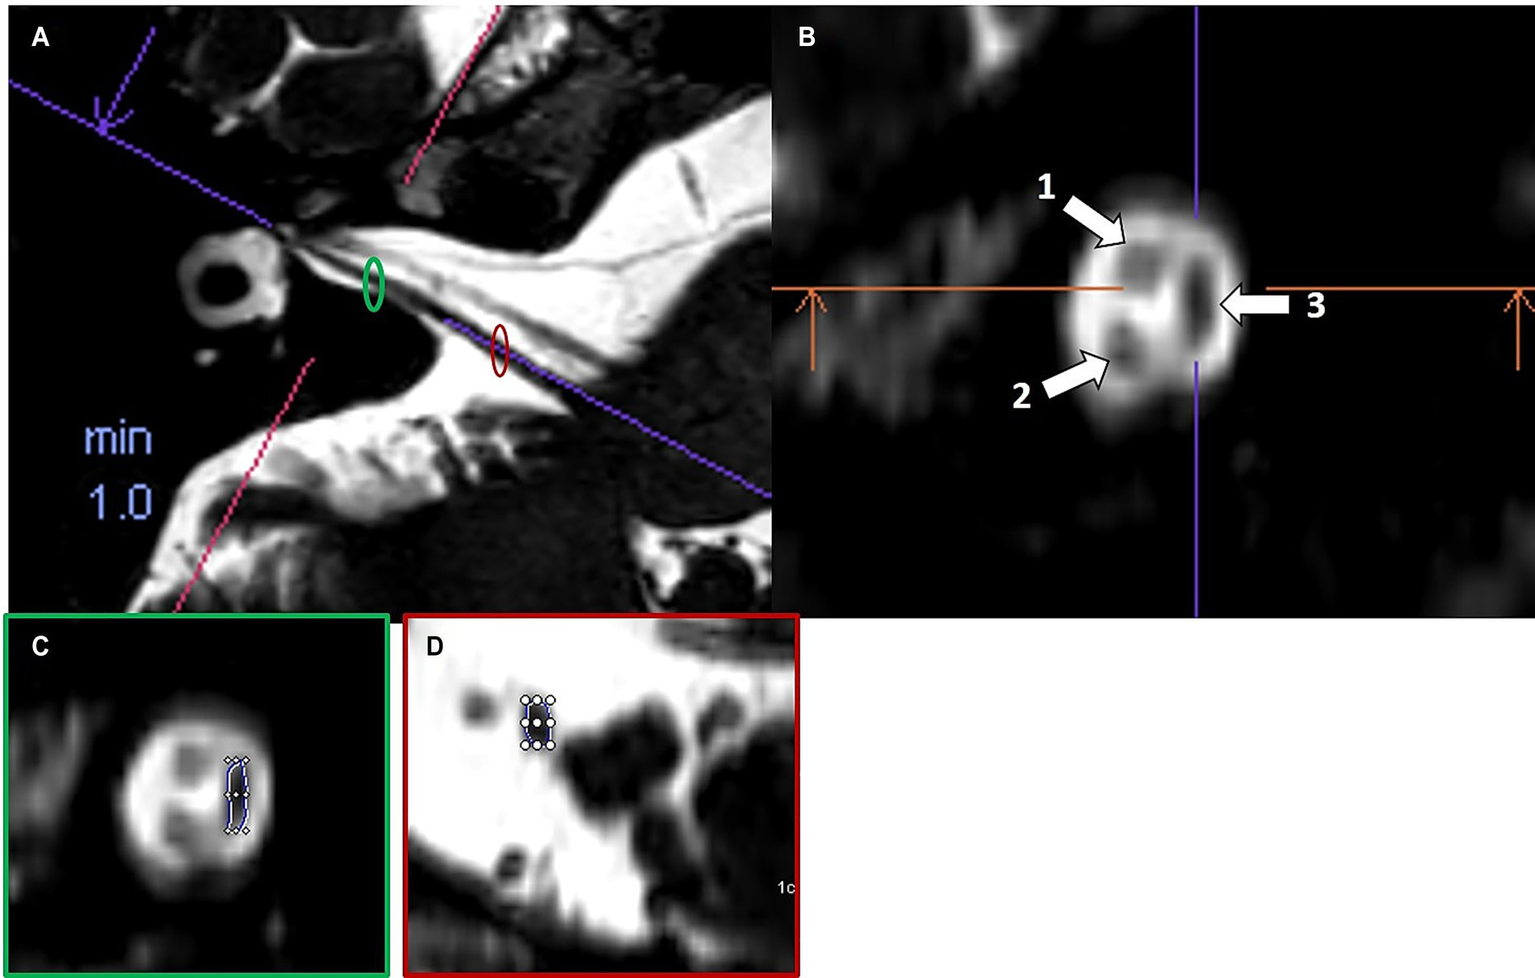

Cochlear and vestibular nerve volumes were measured by AP (a board-certified neuroradiologist holding the European Diploma in Head and Neck Radiology, with more than 6 years’ experience in head and neck imaging), who was blinded to clinical data. A semi-automated segmentation software package (Syngo.via, Siemens Healthineer, version VB80D) was used for volumetric measurements. Bilateral cochlear nerve and vestibular nerve complex volumes were obtained by axis-corrected measurement from the cerebellopontine angle to the IAC fundus. Volume of interest regions were inserted throughout the course of the cranial nerves. The cumulative area of each MRI slice was then calculated by the software to obtain the entire nerve volume. The partial blurring seen at the margins of the reconstructed nerves (penumbra effect) was managed by delineating contours at the midpoint between the central low-signal area and the surrounding high-signal region (Figure 1).

Figure 1

Example of volumetric measurement of the common vestibular nerve. Axial T2w SPACE image (A) at the level of the internal auditory canal showing the orientation of the common vestibular nerve and location of the oblique sagittal 0.8 mm multiplanar reformat from which neural volumetric measurements were obtained. The corresponding oblique sagittal reformatted image (B) at the fundus of the internal auditory canal is positioned lateral to the cochlear aperture with the facial nerve (1), cochlear nerve (2) and the common vestibular nerve (3). Panels (C,D) show sections of the volumetric drawing of the common vestibular nerve, one example in the intrameatal segment (green ellipse) and one example in the cisternal segment (red ellipse).